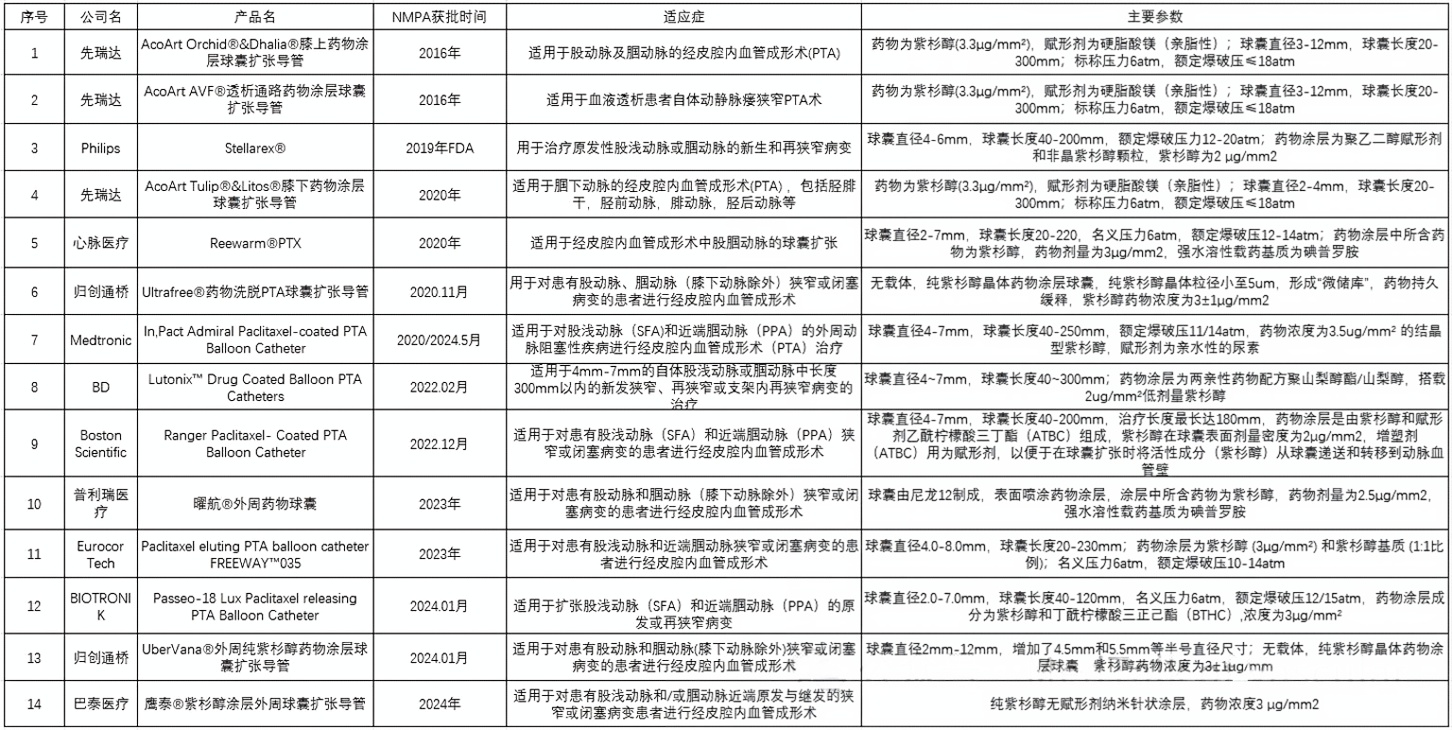

评价DCB的重要指标主要包括以下方面:球囊长度、载体(Excipient carrier)形态和释放机制、运输过程中的损失量、输送量、球囊释放后的残余量、单位表面积的剂量、形态比和药物是否以微粒形式释放等等诸多方面;

截至日前共有14款外周涂层药物球囊获NMPA批准,以下为上市的外周药物涂层球囊的主要信息介绍: